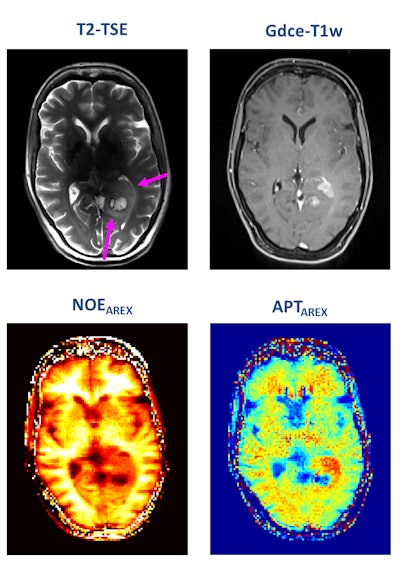

A patient with newly diagnosed glioblastoma underwent relaxation-compensated chemical exchange saturation transfer (CEST) imaging at 7.0 tesla. The protein-weighted CEST contrasts by means of amide proton transfer (APT) and nuclear Overhauser effect (NOE). MRI shows distinct alterations of protein concentrations in the tumor area. While APT signals are markedly increased, NOE-mediated CEST effects drop in the tumor area. The endogenous CEST contrasts have recently proven high potential as novel MR biomarkers to noninvasively assess tumor characteristics and prognosis. (See: Paech D, Windschuh J, Oberhollenzer J, et al, Assessing the predictability of IDH mutation and MGMT methylation status in glioma patients using relaxation-compensated multi-pool CEST MRI at 7.0 T, Neuro-Oncology, November 2018, Vol. 20:12, pp. 1661-1671, and Regnery S, Adeberg S, Dreher C, et al, Chemical exchange saturation transfer MRI serves as predictor of early progression in glioblastoma patients, Oncotarget, June 2018, Vol. 9:47, pp. 28772-28783.) Image courtesy of Dr. Heinz-Peter Schlemmer.Numerous other biomarkers, many of which are functional, are associated with tumors, and these can be quantified with MRI. He pointed out that certain functional biomarkers are readily available, but they have not yet been standardized, and this limits their application at present. Quantification of lesion perfusion over time is a case in point.

Turning to some of the newer imaging methods, he mentioned that chemical exchange saturation transfer (CEST) imaging is showing promise because it allows for the measurement of protein content in the tumor.

"Change in protein content is important. We don't fully understand the biological significance of this, but we have seen meaningful changes, particularly in brain tumors," he noted. "We've also seen a genetic mutation that results in a measureable difference in protein content. We hope that in time we will use CEST for other applications."